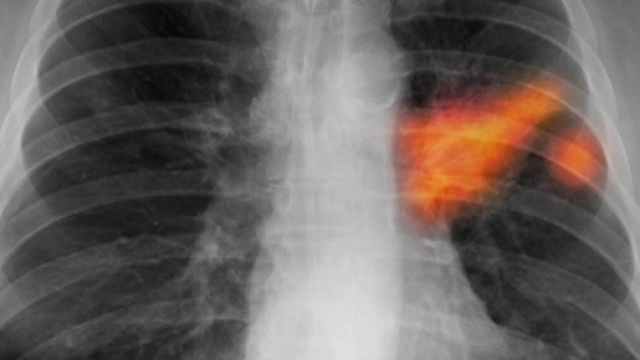

Una rivoluzione nel trattamento del carcinoma polmonare. Un raggio di speranza per centinaia di migliaia di malati in stadio avanzato. Dopo oltre 40 anni, questo tipo di tumore potrebbe non essere più trattato con la chemioterapia che, in molti casi, ha degli effetti indesiderati e alquanto pesanti. L'approccio terapeutico dovrebbe diventare molto più personalizzato, e basato sull'immunoterapia oncologica, in grado di risultare meno invasiva e con minori effetti collaterali rispetto alla chemioterapia. Infatti essa si basa, essenzialmente, sull'uso di farmaci che vanno a potenziare e migliorare le difese immunitarie dell'organismo, che viene così stimolato a distruggere le cellule tumorali.

Il pembrolizumab, prima di ricevere l'approvazione dell'AIFA, è stato testato su circa 300 pazienti, sui quali è stata accertata una riduzione del rischio di morte del 40% circa, e un rallentamento della progressione della malattia di circa il 50%.

Inoltre si è potuto verificare che oltre il 70% dei pazienti sottoposti a trattamento era ancora in vita dopo un anno, mentre in seguito a chemioterapia, la sopravvivenza si attesta al 50%.